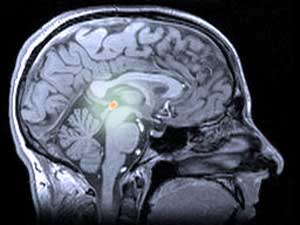

در انسانها و سایر حیوانات، ملاتونین توسط غده پینهای (تلفظ: ‘pie-kneel’) تولید میشود، ساختاری کمی مرموز در عمق مغز. غده پینهای گاهی اوقات به عنوان ‘چشم سوم’ نامیده میشود، زیرا در برخی از مارمولکها، در بالای سر قرار دارد و برای تشخیص سایههای شکارچیان پرنده استفاده میشود.

نور و تاریکی نیز برای غده پینهای انسان و ملاتونینی که تولید میکند مهم هستند. غده پینهای سیگنالهای نوری را از چشمها دریافت میکند و هنگام تاریکی ملاتونین آزاد میکند. ملاتونین بر مراکز خواب مغز تأثیر میگذارد و باعث خواب آلودگی ما میشود. در درازمدت، کاهش روزانه و افزایش شبانه ملاتونین، الگوی خواب و بیداری ما را تنظیم میکند و آن را با تغییرات نور روز هماهنگ نگه میدارد.